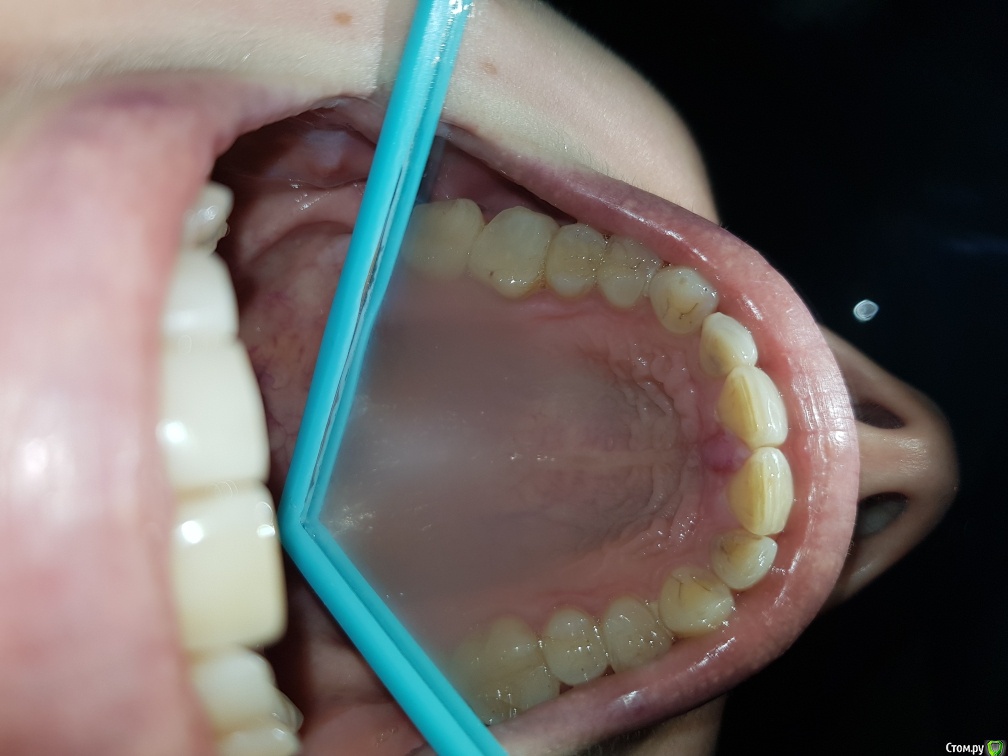

Здравствуйте. 10 мая 2019 года мне сделали эстетическую реставрацию диастемы между передними зубами. Через 2 дня воспалился резцовый сосочек. Лечили Метрогил Дента, Холисал, полоскание солью, пародонтолог прижигал сосочек 3 раза. Ничего не помогло. Сделали КТ- все в норме, была на консультации у хирурга - ничего не видят, проблему не могут найти. Два раза шлифовали пломбу. Помогите установить причину. КТ по ссылке на гугл диске

post-58052-0-88761800-1561453156_thumb.jpg